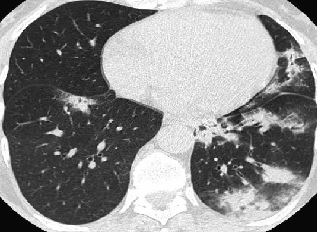

程大叔的胸部CT

程大叔来到某医院,医生给他做了一个胸部CT,结果却让他大吃一惊,CT提示:双肺多发结节,性质待定,考虑到程大叔 50多岁,长期抽烟,这可是妥妥的肿瘤高危人群啊,现在又是咳嗽又是胸痛的,难道真的是肺癌?